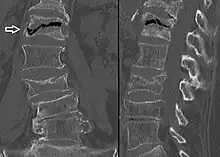

Front X-ray of right knee of an adolescent (epiphyseal plates are open): arrows point to avascular necrosis and developing osteochondritis dissecans in the outer medial condyle of femur

In the early stages, bone scintigraphy and MRI are the preferred diagnostic tools.[12]

X-ray images of avascular necrosis in the early stages usually appear normal. In later stages it appears relatively more radio-opaque due to the nearby living bone becoming resorbed secondary to reactive hyperemia.[2] The necrotic bone itself does not show increased radiographic opacity, as dead bone cannot undergo bone resorption which is carried out by living osteoclasts.[2]